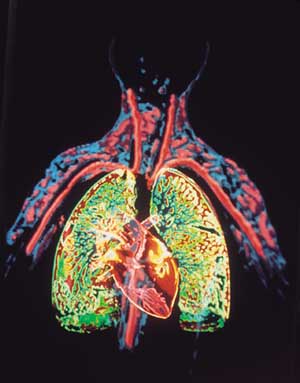

القلب Heart عضو عضلي يضخ الدم في جسم الإنسان. ومع كل دقّة يدفع القلب الدم الضروري للحياة عبر جسم الإنسان. ويحمل الدم الأكسجين والغذاء لكل خلايا الجسم وتبدأ دقات القلب ذات الإيقاع المنتظم قبل سبعة أشهر من ميلاد الطفل تقريبًا. وعندما يتوقف القلب تتوقف الحياة، إلا إذا ساعدت أجهزة آلية خاصة على دوران وأكسجة الدم. والقلب عضو عضلي مجوّف كبير، ينقسم إلى مضختين متجاورتين. وتنقل الأوردة الدموية الدم في جميع أنحاء الجسم إلى المضخة الواقعة في الجهة اليمنى التي ترسله بدورها إلى الرئتين لحمل الأكسجين، ومن ثم، ينساب الدم المؤكسد إلى الجهة اليسرى من القلب التي تضخه إلى أجزاء الجسم المختلفة بوساطة الشرايين. وهناك صمامات تتحكم في سريان الدم داخل القلب. والمضخة اليسرى، التي تدفع الدم إلى جميع أنحاء الجسم أقوى وأكبر حجمًا من المضخة اليمنى. والقلب والتشكيلات الأنبوبية الأخرى مثل الشرايين والأوردة والشعيرات تسمى جميعًا الجهاز الدوري أو الجهاز القلبي الوعائي. ينظم الجهاز العصبي عمل القلب وأجزاء أخرى من الجهاز الدوري. وينظم الجهاز العصبي التلقائي، وهو جزء من الجهاز العصبي، ضربات القلب (النبض)، فيقللها أو يزيدها حسب حاجة الجسم؛ لذلك فإن القلب يدق بصورة هادئة مثلاً عندما يكون الإنسان نائمًا ويزود الجسم بكمية قليلة نسبياً من الأكسجين. وقد تزداد سرعة ضربات القلب مرة أخرى لتزيد كمية مردود الأكسجين للجسم بغزارة. ويحدث هذا عندما يزاول الإنسان التمارين الرياضية أو عندما يصاب بالخوف أو عندما يحتاج للمقاومة أو العراك أو الجري. وقد يصيب المرض أو الخلل أي جزء من أجزاء القلب أو الأوعية الدموية، ويعتبر ذلك من الأسباب الرئيسية للوفاة في البلدان الصناعية. وأكثر أمراض القلب شيوعًا هي التي تصيب الشرايين التي تغذي القلب نفسه بالدم. والخلل الذي يصيب هذه الشرايين قد يتطور مع سنوات عمر الإنسان. فترسُّب المواد الدهنية مثلاً، يؤدي إلى انسداد شرياني وإلى قلة كمية الدم التي تزود القلب. وإذا استقبلت عضلة القلب كمية قليلة من الدم فإن هذا قد يؤثر في أدائها أو إلى موتها. ويسمى هذا الخلل أو التلف الناتج من قلة إمداد عضلة القلب بالدم النوبة القلبية. والنوبة القلبية الخفيفة قد تجبر الإنسان لكي يعيش حياة أقل نشاطًا وحركة. أما النوبة القلبية القاسية أو العنيفة فتجعل القلب غير قادر على إمداد الجسم بكمية كافية من الدم، حتى في حالة الراحة الكاملة، وقد تؤدي إلى الوفاة. وقد تصيب الأمراض أجزاء أُخرى من القلب وقد يؤدي هذا إلى تأثير مدمّر مشابه. تحققت أهم التطورات الطبية الحديثة في مجال طب القلب، وهو حقل طبي يعنى بالأمراض التي تصيب القلب والأوعية الدموية. ومنذ آلاف السنين، لم يكن مرضى القلب يعرفون أصلاً أن لهم هذه المشكلة. وفي التسعينيات من القرن العشرين الميلادي، تعلم الأطباء كيف يشخصون ويعالجون بعض حالات مرض القلب التي كان علاجها علاجها مستحيلاً في السابق، وكانت تعني الوفاة لمن يصاب بها. وأدّى اكتشاف الأدوية والتطور الهائل في الجراحة إلى إعطاء عدد من مرضى القلب أملاً في الحياة، وبدأ الأطباء بزراعة القلوب بل طوّروا أجهزة تقوم بعمل القلب مؤقتًا. واليوم تُجرى كثير من الأبحاث في علم القلب ووظائفه، ويتم التركيز على دراسة الأسباب التي تؤدي إلى أمراض القلب حتى يمكن تفاديها. وتدرس أبحاث أخرى إمكانية خفض حالات الموت والعجز التي تنتج من أمراض القلب، عن طريق دعم وتطوير أدوية وعقاقير معالجة جديدة واستحداث قلب صناعي فعّال. هذه المقالة عن قلب الإنسان بصورة خاصة، والجزء الأخير منها يصف قلب الحشرات والسمك والطيور والحيوانات الأخرى. ولمزيد من المعلومات عن عمل الدم في الجسم،

تشكل العضلة القلبية النسيج الفعال وظيفيا من القلب حيث يؤمن تقلصها انتقال الدم وضخه من القلب إلى باقي الأعضاء مما يجعل القلب محطة الضخ الرئيسية للدم من القلب إلى العضاء لتزويدها بالأكسجين المحمل في الدم القادم من الرئتين, من ثم يقوم القلب بضخ الدم القادم من العضاء والمحمل بثاني أكسيد الكربون إلى الرئتين لتنقيته و تحميله من جديد بالأكسجين.

يحتوي الدم الذي يدخل الجانب الأيمن من القلب على ثاني أكسيد الكربون، وهو غاز فاسد تفرزه الخلايا والأنسجة في عملية إنتاج الطاقة. ويدخل الدم الأذين الأيمن عن طريق الوريد الأجوف العلوي والوريد الأجوف السفلي. وعندما يمتلئ الأذين ينقبض، ضاخًا الدم في البطين. وحينما يمتلئ البطين فإن الضغط المتولد يجعل الصمام المثلث الشرف ينغلق، والصمام الرئوي المؤدي للشريان الرئوي ينفتح، وبعدها ينقبض البطين ويدفع الدم في الشريان الرئوي ثم إلى الرئتين. وفي الرئتين يستبدل الأكسجين بثاني أكسيد الكربون. ثم ينساب الدم المؤكسد في الأوردة الرئوية للجزء الشمالي من القلب. انظر: الرئة.